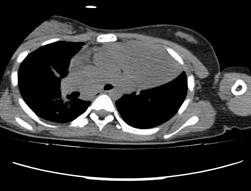

Se indicó que le tomaran una tomografía axial computarizada (TAC) de tórax, donde se observó una masa de 17 mm en el interior de la luz distal del bronquio fuente izquierdo con obstrucción de la luz para el lóbulo superior (LS). Se evidenció consolidación y pérdida de volumen del lóbulo superior izquierdo, hiperinflación y atelectasia parcial del lóbulo inferior izquierdo y nódulos centrilobulillares en los segmentos basal posterior y lateral del lóbulo inferior izquierdo. Los anteriores hallazgos eran compatibles con tumor endobronquial (figura 2).